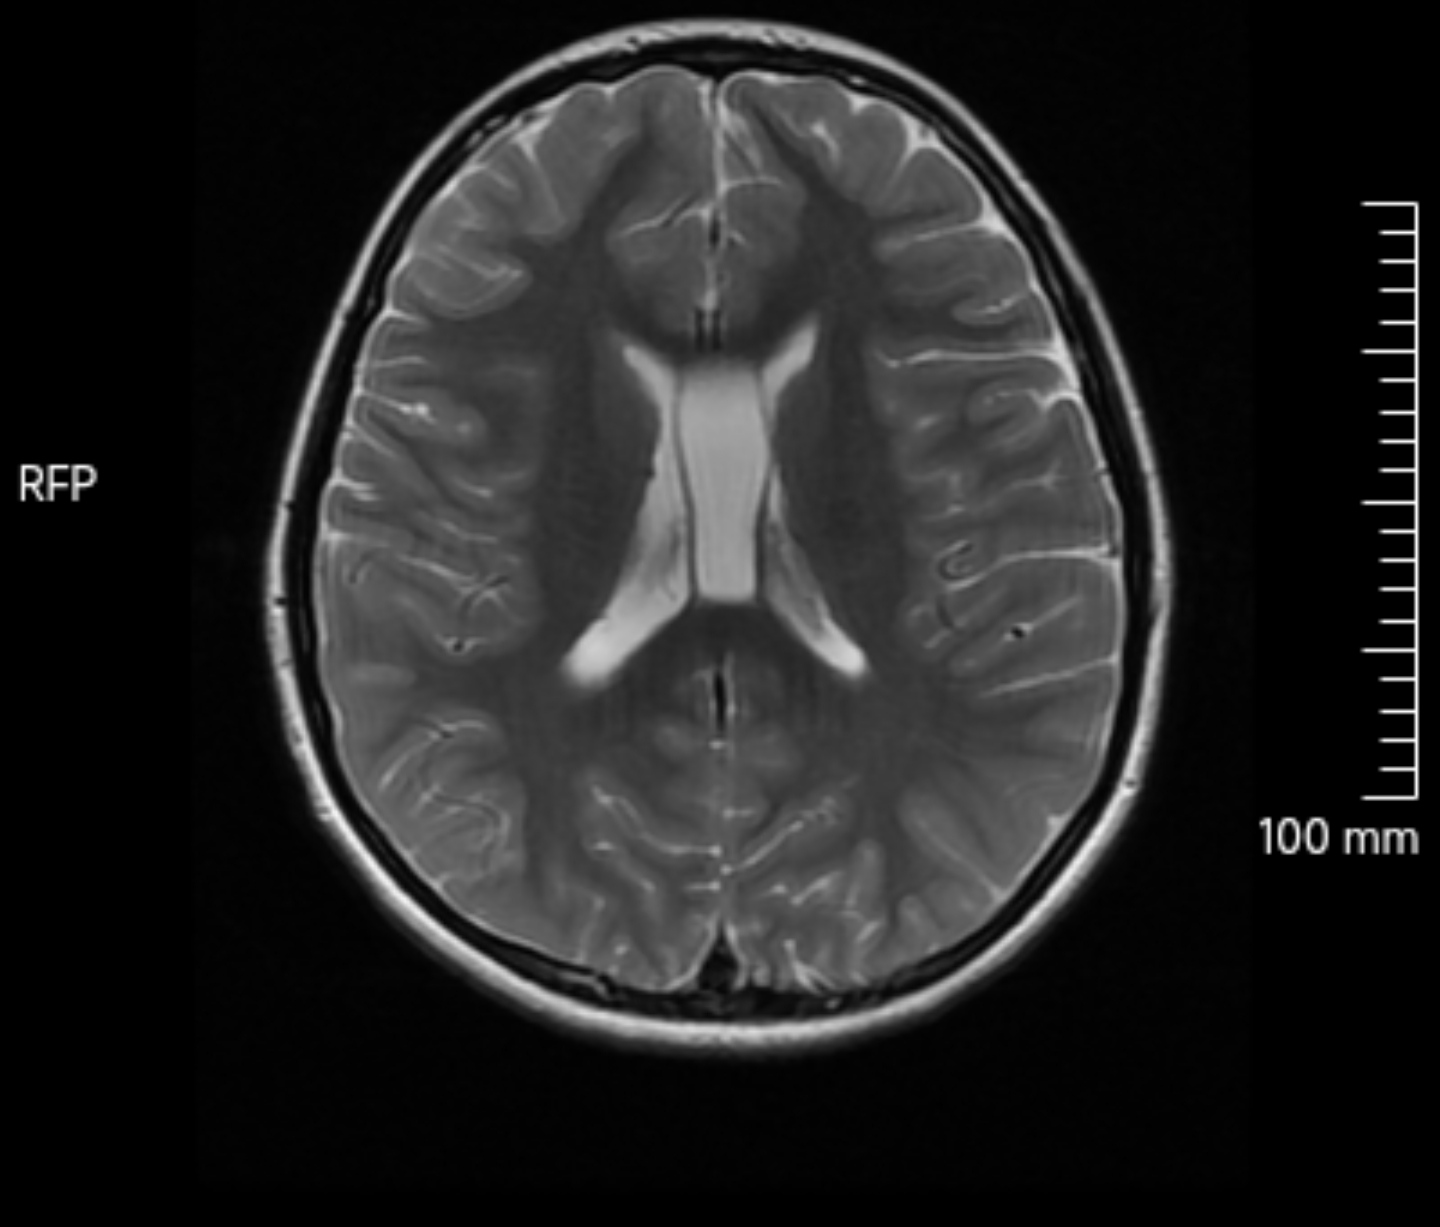

透明隔囊肿